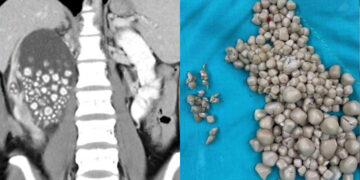

Οι γιατροί στην πόλη Taina της Ταϊβάν ήρθαν αντιμέτωποι με μια ιδιαίτερα σπάνια περίπτωση, όταν μία 20χρονη γυναίκα μεταφέρθηκε στο νοσοκομείο με έντονους πόνους στο κάτω μέρος της πλάτης.

Η νεαρή γυναίκα εμφάνιζε επίσης πυρετό και εξετάσεις αίματος αποκάλυψαν αυξημένο αριθμό λευκών αιμοσφαιρίων. Μια αξονική τομογραφία επιβεβαίωσε το εύρημα που άφησε άφωνους τους γιατρούς: το δεξί νεφρό της ήταν γεμάτο πέτρες.

Αρχικά της χορηγήθηκαν αντιβιοτικά, ωστόσο λόγω της κατάστασης προχώρησαν σε χειρουργική επέμβαση, κατά την οποία αφαιρέθηκαν πάνω από 300 λίθοι, με μέγεθος που κυμαινόταν από 5 χιλιοστά έως και 2 εκατοστά.